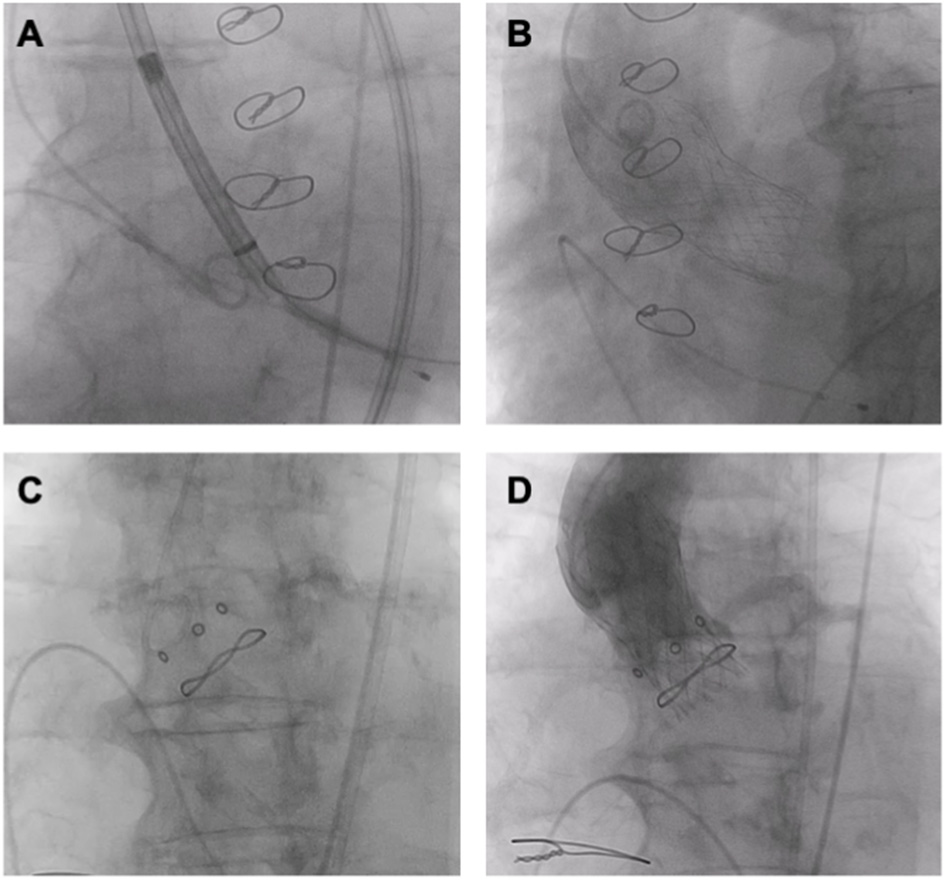

Figure 6

ViV TAVR. (A,B) ViV (Medtronic Evolut R 29 mm in Trifecta 25 mm). (C,D) ViV (Medtronic Evolut R 23 mm in Hancock II 21 mm).